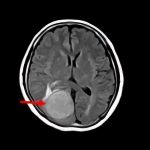

断層撮影

手術前1

手術前2